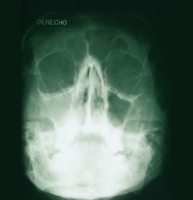

Llevat del refredat o l'al·lèrgia, la sinusitis bacteriana requereix diagnòstic mèdic i tractament antibiòtic per guarir la infecció i prevenir futures complicacions. Normalment, les mucositats acumulades en els sinus drenen a través dels conductes nasals. Quan és a causa d'un refredat o d'una al·lèrgia, els sinus s'inflamen i no poden drenar. Això ens pot dur a una congestió i infecció. El diagnòstic de la sinusitis aguda es basa en una exploració física i l'explicació per part del pacient dels símptomes. Pot caldre una radiografia i una mostra de la mucositat per analitzar el bacteri.